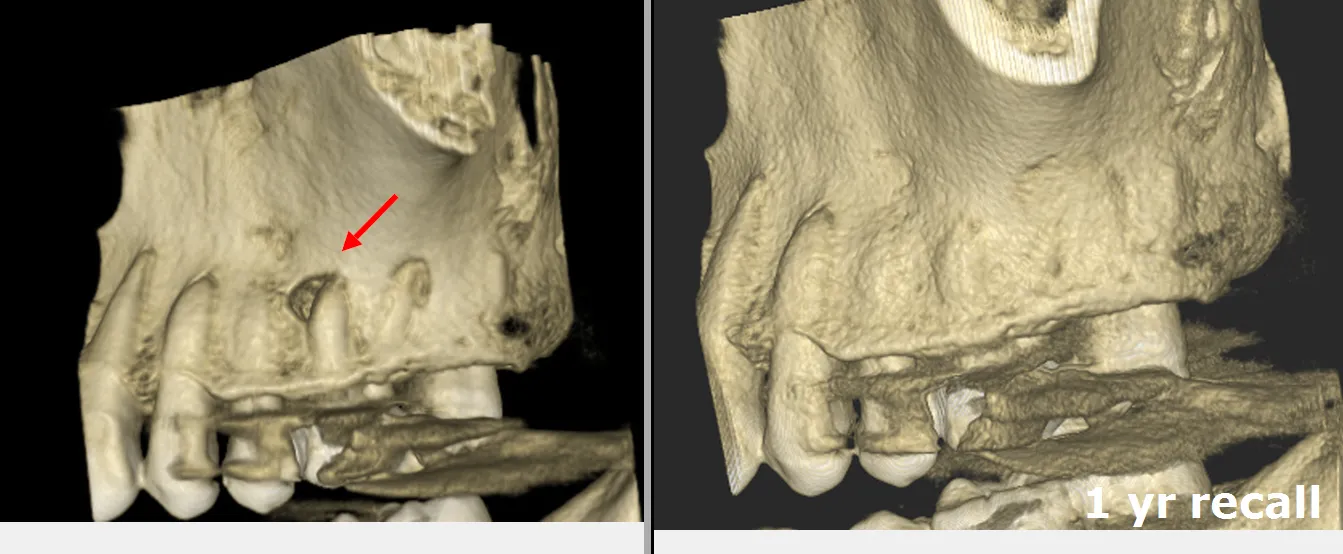

Severely calcified MB2 canal not located during initial treatment—CBCT showed complete sclerosis

The referring dentist had completed what appeared to be adequate endodontic treatment two years prior, but the patient continued to experience intermittent discomfort and sensitivity to percussion. Clinical examination revealed no obvious defects, but CBCT imaging told a different story: a completely calcified MB2 canal with associated periapical pathology.

At 2-year follow-up, the patient remains completely asymptomatic with radiographic evidence of periapical healing. The tooth is functional and the patient reports no sensitivity.